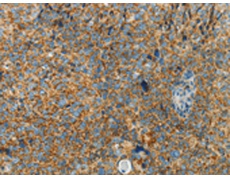

IHC positive control: |

Human cervical cancer and human thyroid cancer |

IHC Recommend dilution: |

100-300 |